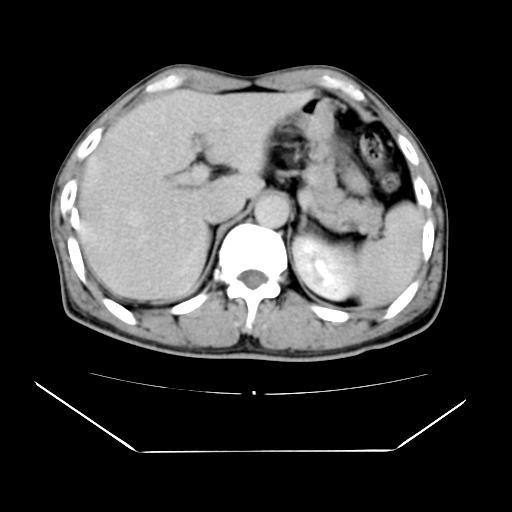

男性,55岁,外院体检afp明显升高,但b超未发现异常,否认乙肝病史。来我院ct增强。有延时扫描。

延时扫描完全充填,血管瘤

肝脏右叶动脉期可见低密度影,至延迟期被充填,考虑血管瘤可能性大。

肝右叶病灶

不排除肝右叶肝癌可能。

如果这个是癌灶的话则下腔静脉有瘤栓可能

肝6段血管瘤

血管瘤可能性大。

考虑肝右静脉影。